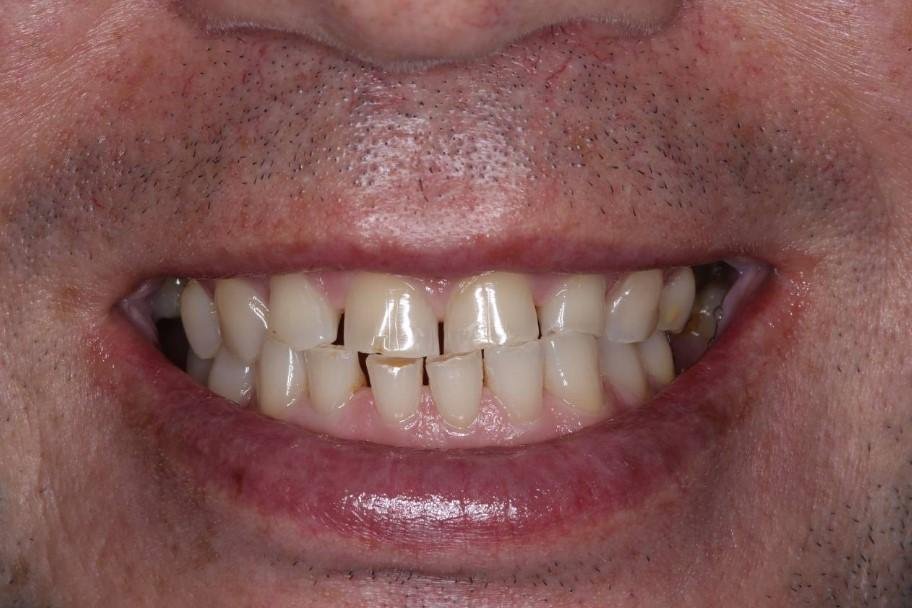

Как выглядел профиль пациента (фото)